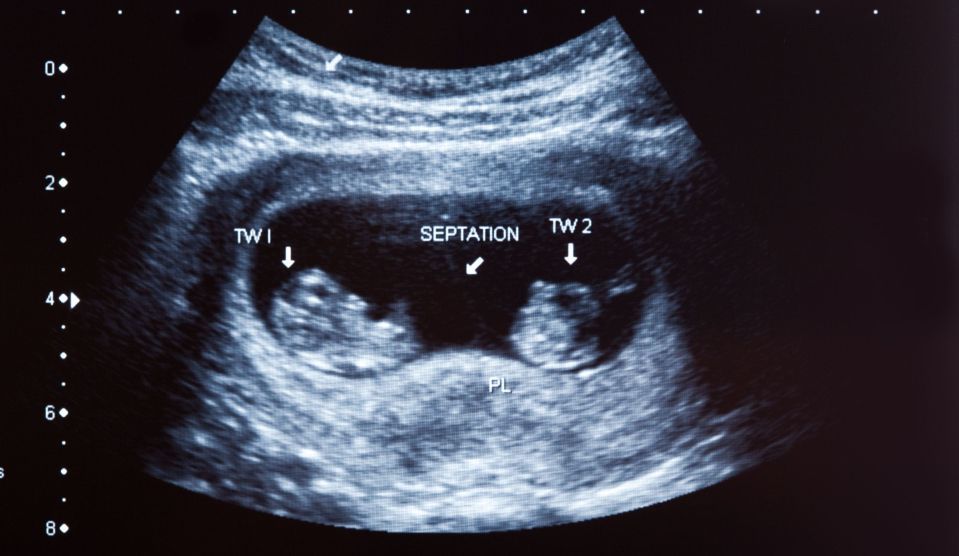

Bebeluşul, care a avut la naştere 2,9 kilograme, a venit pe lume marţi, într-un spital din Grecia, şi atât acesta, cât şi mama, o femeie în vârstă de 32 de ani, se simt bine. Mama urmase în prealabil patru sesiuni de fertilizare in vitro.

Mai precis, medicii au folosit un ovul prelevat de la mamă, spermă de la tată şi un alt ovul de la o donatoare, iar tehnica a fost dezvoltată în principiu pentru a ajuta familiile care se confruntă cu maladii mitocondriale letale pe care mama le poate transmite copilului.

Tehnica presupune scoaterea nucleului din ovulul mamei, implantarea lui în ovulul golit de nucleu al donatoarei şi apoi fertilizarea cu material genetic de la tată. Ovulul astfel obţinut este implantat în uterul mamei.

Astfel, bebeluşul născut marţi a moştenit şi o cantitate mică de ADN de la donatoare, cel al mitocondriilor, moştenind genetic trei părinţi.